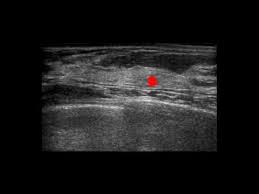

Ultrasound does not use or. 47 year old female presented with a painless but palpable left breast lump. Other ultrasound findings that suggest breast cancer include: We'll show you breast cancer pictures to help you identify any physical traits of the condition. Below are images of dcis on breast ultrasound. But radiologists can still see signs of cancer. What does breast cancer look like on a mammogram? Breast cancer is among the most common causes of cancer deaths today, coming fifth after lung, stomach, liver and colon cancers. Other ultrasound findings that suggest breast cancer include: The breast tissue kind of looks like waves on the ocean. Is tender, aches or feels painful. Ultrasound images are black and white, showing a small portion of the breast at a time. It is an infiltrating, malignant and abnormal proliferation of neoplastic cells in the breast tissues.

47 year old female presented with a painless but palpable left breast lump. The sound waves pass through the breast and bounce back or echo from various tissues to form a picture of the internal structures of the breast. But there are signs to look out for that could indicate something more serious. Inflammatory breast cancer pictures and symptoms. What does a cancerous breast lump look like on ultrasound? Inflammatory breast cancer is an infrequent, aggressive type of breast cancer that spreads rapidly. The person operating the ultrasound will sweep, or fan, the probe back and forth to look at different areas in 90 degree angle images. Generally speaking, the denser the tissue, the whiter it appears.

Inflammatory breast cancer, also known as carcinomatous mastitis, t4d, or pev 2 or 3, is the only real therapeutic emergency in breast oncology, given the high risk of metastasis, the reason for the most unfavourable prognosis of all breast cancers.it must consequently be diagnosed rapidly, and imaging examinations must in no case delay therapeutic management. Is tender, aches or feels painful. Generally speaking, the denser the tissue, the whiter it appears. The symptoms of ibc include a breast that: Finding breast lumps and seeing change in the size and shape. This breast cancer ultrasound image shows changes related to breast cancer that are not seen as microcalcifications or a mass or lump. The mass is hypoechoic with posterior shadowing (orange arrow), taller than wide and moderate vascularity. Although mammography is more specific, ultrasound is a very important tool in making the diagnosis of fat necrosis. Depending on your symptoms, your doctor makes a diagnosis based on a combination of tests and procedures. The sound waves pass through the breast and bounce back or echo from various tissues to form a picture of the internal structures of the breast. Breast ultrasound breast ultrasound uses sound waves to make a computer picture of the inside of the breast. My doctor found a lump in my breast during my yearly mammogram and then brought in an ultrasound technician to follow up with an ultrasound for a closer look. Inflammatory breast cancer pictures and symptoms.